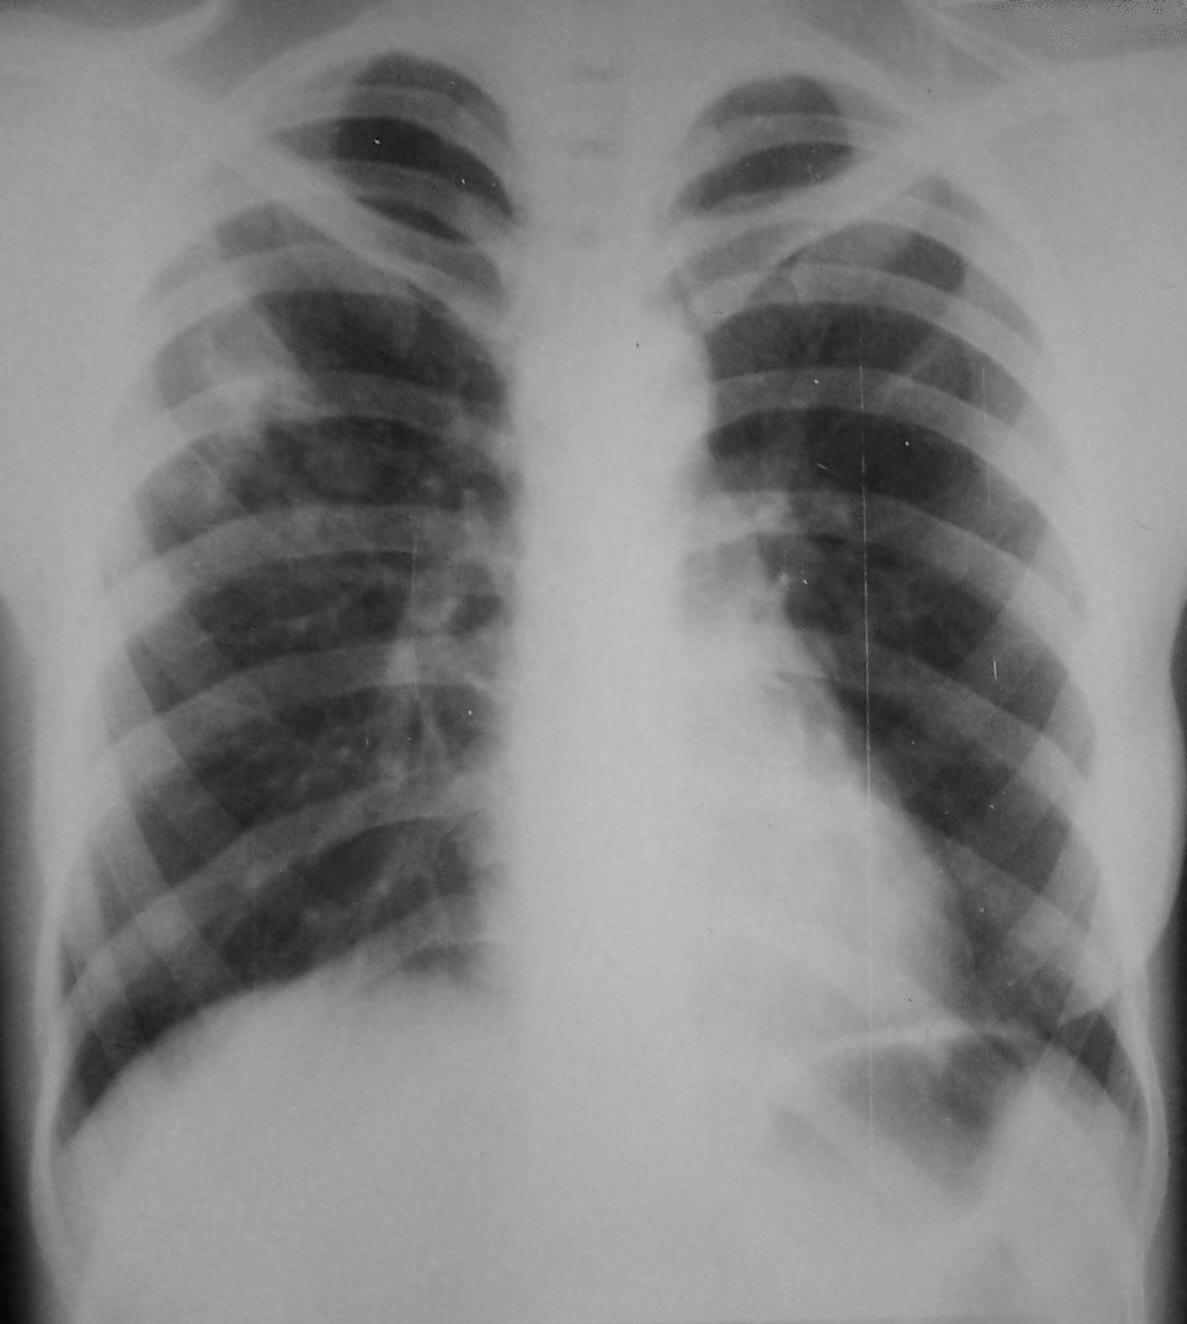

Рис. 4. Обзорная рентгенограмма органов грудной клетки больной С., 24 года в процессе лечения, где:

а) прямая проекция;

б) боковая проекция.

Однако при контрольном рентгенологическом исследовании органов грудной клетки от 25.03.2005 г. выявлено: в S1, S2, S3 правого легкого инфильтрация легочной ткани. На фоне инфильтрации крупные округлые очаги. В S2 полость распада. Умеренная перибронхиальная инфильтрация (Рис. 5). Компьютерная томография от 28.03.2005 г.: в верхней доле правого легкого инфильтрация с множественными полостями распада, очагами различной плотности. Слева в S4-S5 инфильтрация легочной ткани с мелкими полостями распада (рис. 6).

Рис. 5. Обзорная рентгенограмма органов грудной клетки больной С., 24 года в процессе лечения, где: